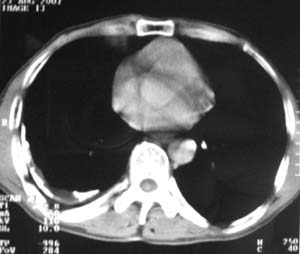

标题: CT9556:男,54岁,包裹性积液,请各位老师会诊其原因! [打印本页]

男,54岁,无任何不是感.体检发现右肺部阴影.现行ct进一步确诊.

右侧胸廓塌陷,肋间隙变窄,肋骨增生变粗,脏壁层胸膜肥厚、钙化。符合陈旧性结核性脓胸改变

右侧胸膜肥厚、粘连、钙化。

右测包裹性积液并胸膜钙化,结核性脓胸还是胸膜肿瘤转移,还需要穿刺抽液